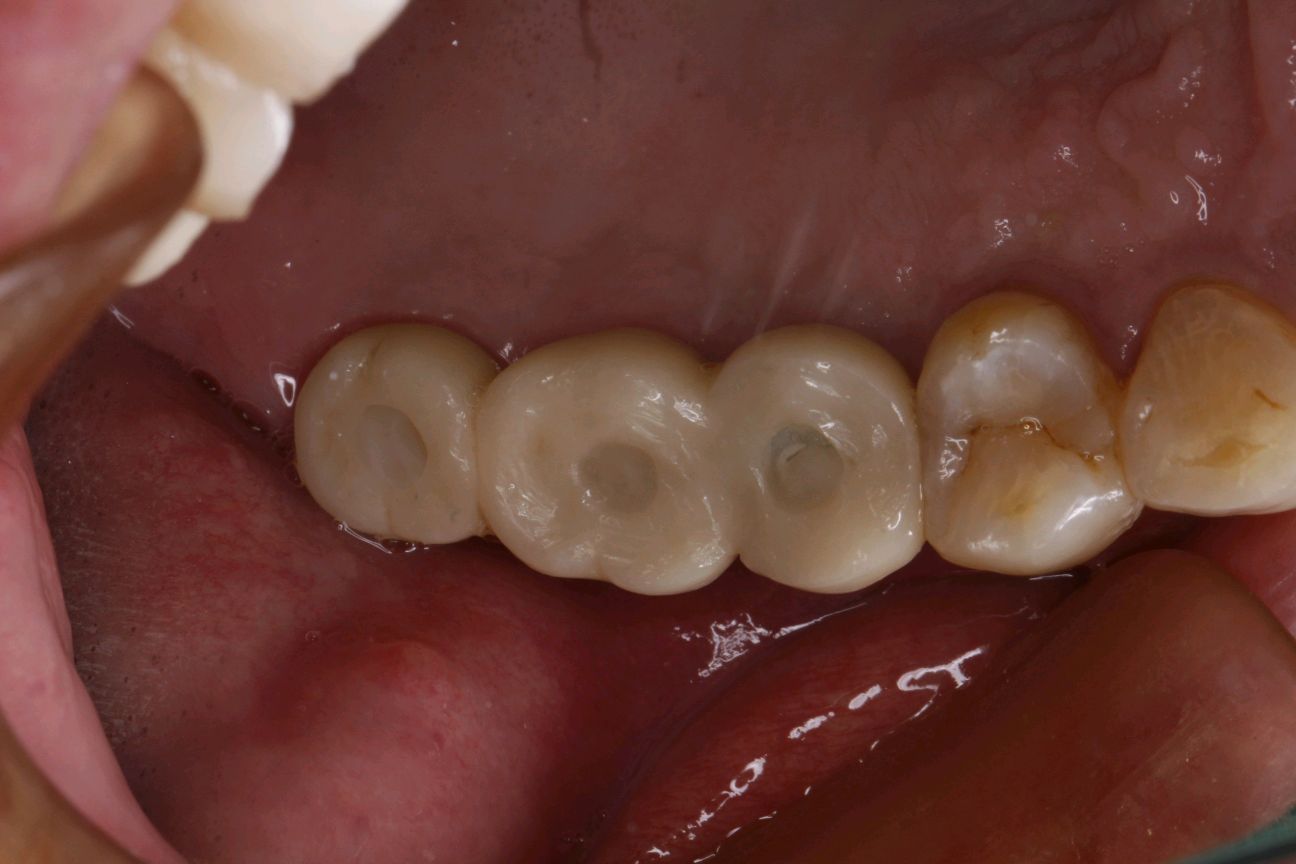

完成戴牙

调合、抛光。患者对修复体形态颜色满意,确认后,基台加扭力35Ncm。置入特氟龙胶布,用双重固化树脂(RelyxUltimateClicer)做永久固定,清理多余粘固材料,固化,调合,抛光。